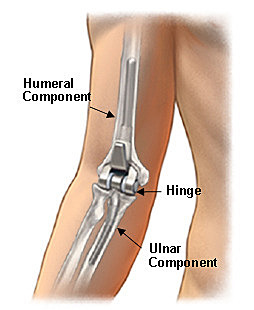

• First Attempt to Replace an Elbow With Prosthetic Materials

First Attempt to Replace an Elbow With Prosthetic Materials

In 1925, the first attempt to replace an elbow joint by prosthetic materials was documented, when a doctor inserted an anatomically correct elbow prosthesis, consisting of metal and hardened rubber.

• First hinged Elbow Replacement

First hinged Elbow Replacement

In 1941, another doctor used a hinged non-anatomical prosthesis completely made of metal

• Dr. Dee Reported the First Functionally Designed Total Elbow Arthoplasty (TEA)

Dr. Dee Reported the First Functionally Designed Total Elbow Arthoplasty (TEA)

Dr. Dee designed the first functional TEA in 1972. This initiated an increase in various TEA models throughout the 1970’s. Designing a TEA is a very difficult task as it has to copy the native function and stability of all three articulations in the elbow joint. TEA considerably improves the upper limb and increases the quality of life. This is why it is a great option for people who suffer from a decreased range of motion in their elbow caused by primary osteoarthritis or trauma.